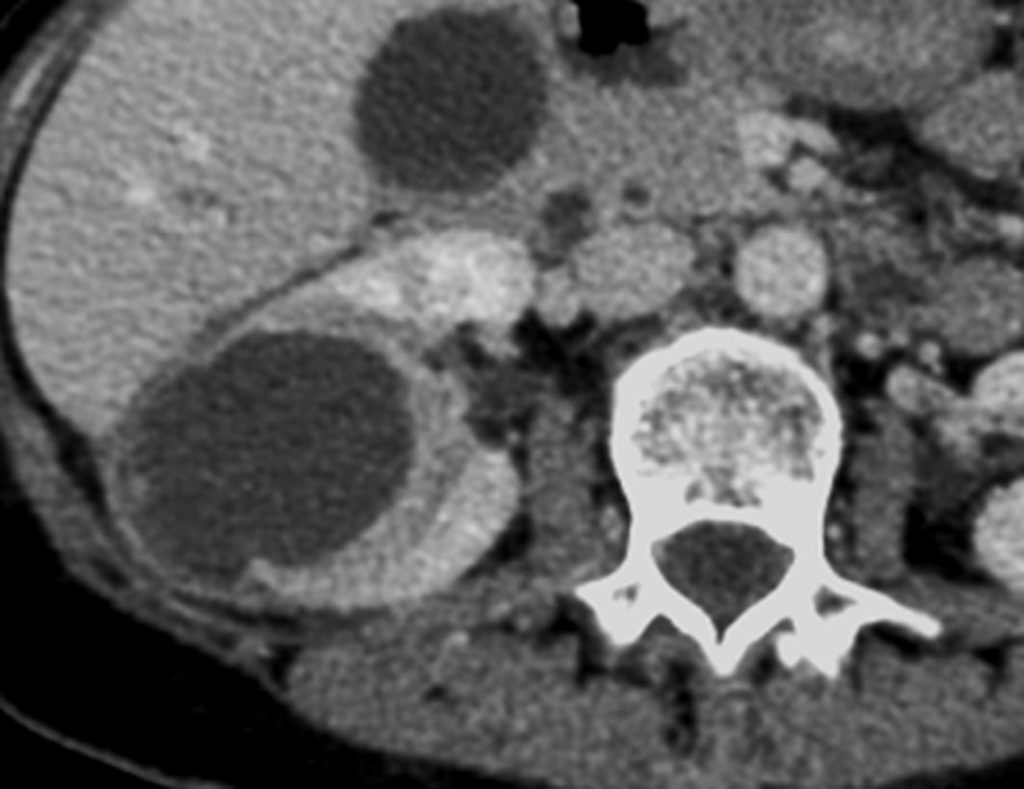

- abcès du rein : collection intrarénale arrondie organisée, avec une coque qui se rehausse après injection et avec une composante centrale purulente de densité liquidienne (figure 26.2), parfois associée à une extension périrénale (figure 26.3) ;

Fig. 26.2. Abcès rénal. Scanner après injection de produit de contraste iodé au temps tubulaire.

Abcès rénal collecté avec une coque et un contenu de densité liquidienne.

Source : CERF, CNEBMN, 2022.